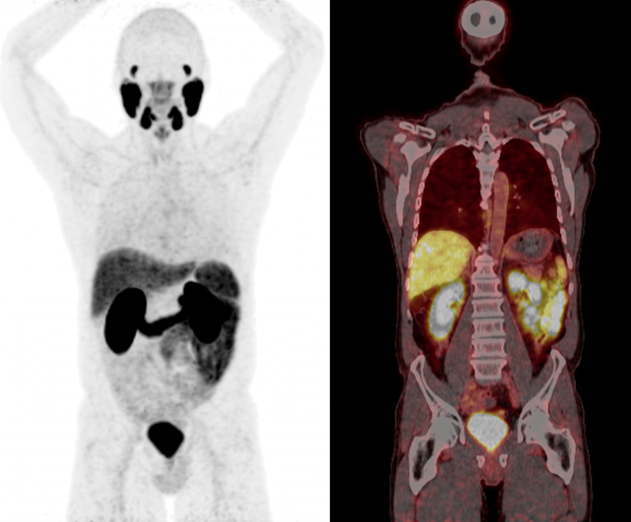

PSMA PET-CT是一种新型的医学影像检查技术,用于诊断前列腺癌及其转移情况。它结合了分子靶向PET影像和CT影像的优势,能够更准确地定位前列腺癌的位置和范围,同时发现转移病灶。

这种技术基于前列腺特异性膜抗原(PSMA)的表达情况,通过靶向PSMA进行分子成像,能够提供更精确的诊断信息。通过PSMA PET-CT检查,医生可以更好地评估前列腺癌的病情,制定个性化的治疗方案,同时也能帮助患者更了解自己的疾病情况,对接下来的治疗和生活做出更明智的决策。

目前市面上主要用于PSMA PET-CT检查的显像剂是[68Ga]Ga-PSMA-11和[18F]PSMA-1007。这些显像剂可以作为靶向剂与前列腺特异抗原(PSMA)结合,从而在PET-CT扫描中提供更精确的前列腺癌肿瘤成像。

与传统影像学(CT/MRI)相比:相比传统影像学,PSMA PET-CT可以更准确地定位前列腺癌的原发病灶和转移灶,尤其在早期病变的诊断方面具有优势。由于PSMA PET-CT可以显示PSMA在前列腺癌细胞上的表达,因此在区分肿瘤组织和正常组织时更为精准,能够提供更细致的肿瘤定位信息。其次,PSMA PET-CT的分子级别成像能力使其在评估前列腺癌的肿瘤生物学特征上具有优势,有助于个性化治疗方案的制定。而且,PSMA PET-CT还可以更早地检测出微小的转移病灶,提高了治疗的精准性和效果。

与传统FDG PET-CT检查相比:PSMA PET-CT对前列腺癌的特异性更高,能够更准确地定位前列腺癌的病灶,而18-F FDG PET-CT在前列腺癌的诊断中的特异性较低。其次,PSMA PET-CT在评估前列腺癌的转移情况上更为敏感,特别是对骨转移的检测,相比18-F FDG PET-CT更加准确。此外,PSMA PET-CT还能够提供更为精准的肿瘤定位和生物学特征表达信息,有助于更精准地制定治疗方案。